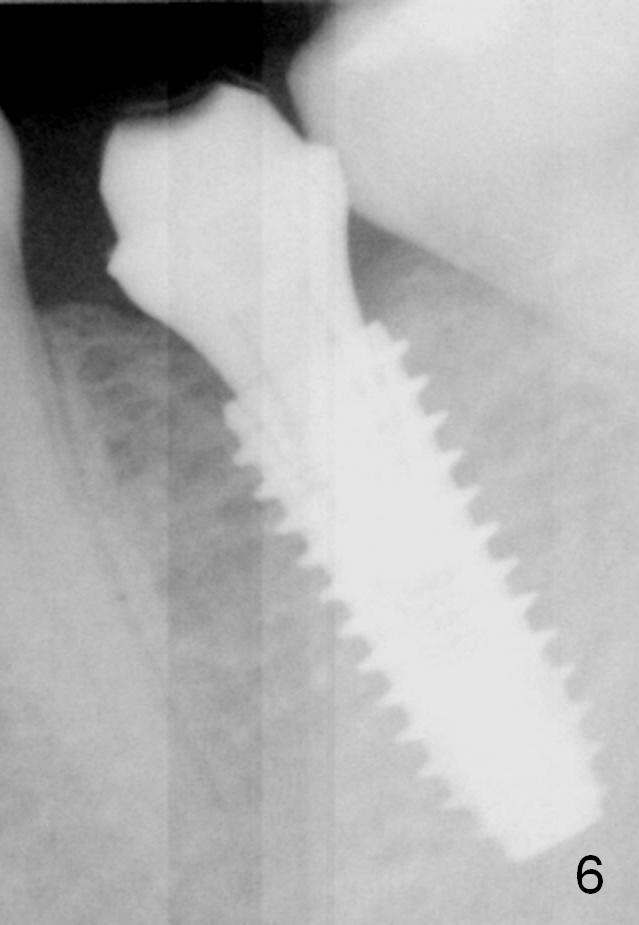

There is no bone loss 3 months postop (Fig.6).  Mesial laser gingivectomy and lingual margin prep are conducted prior to impression.